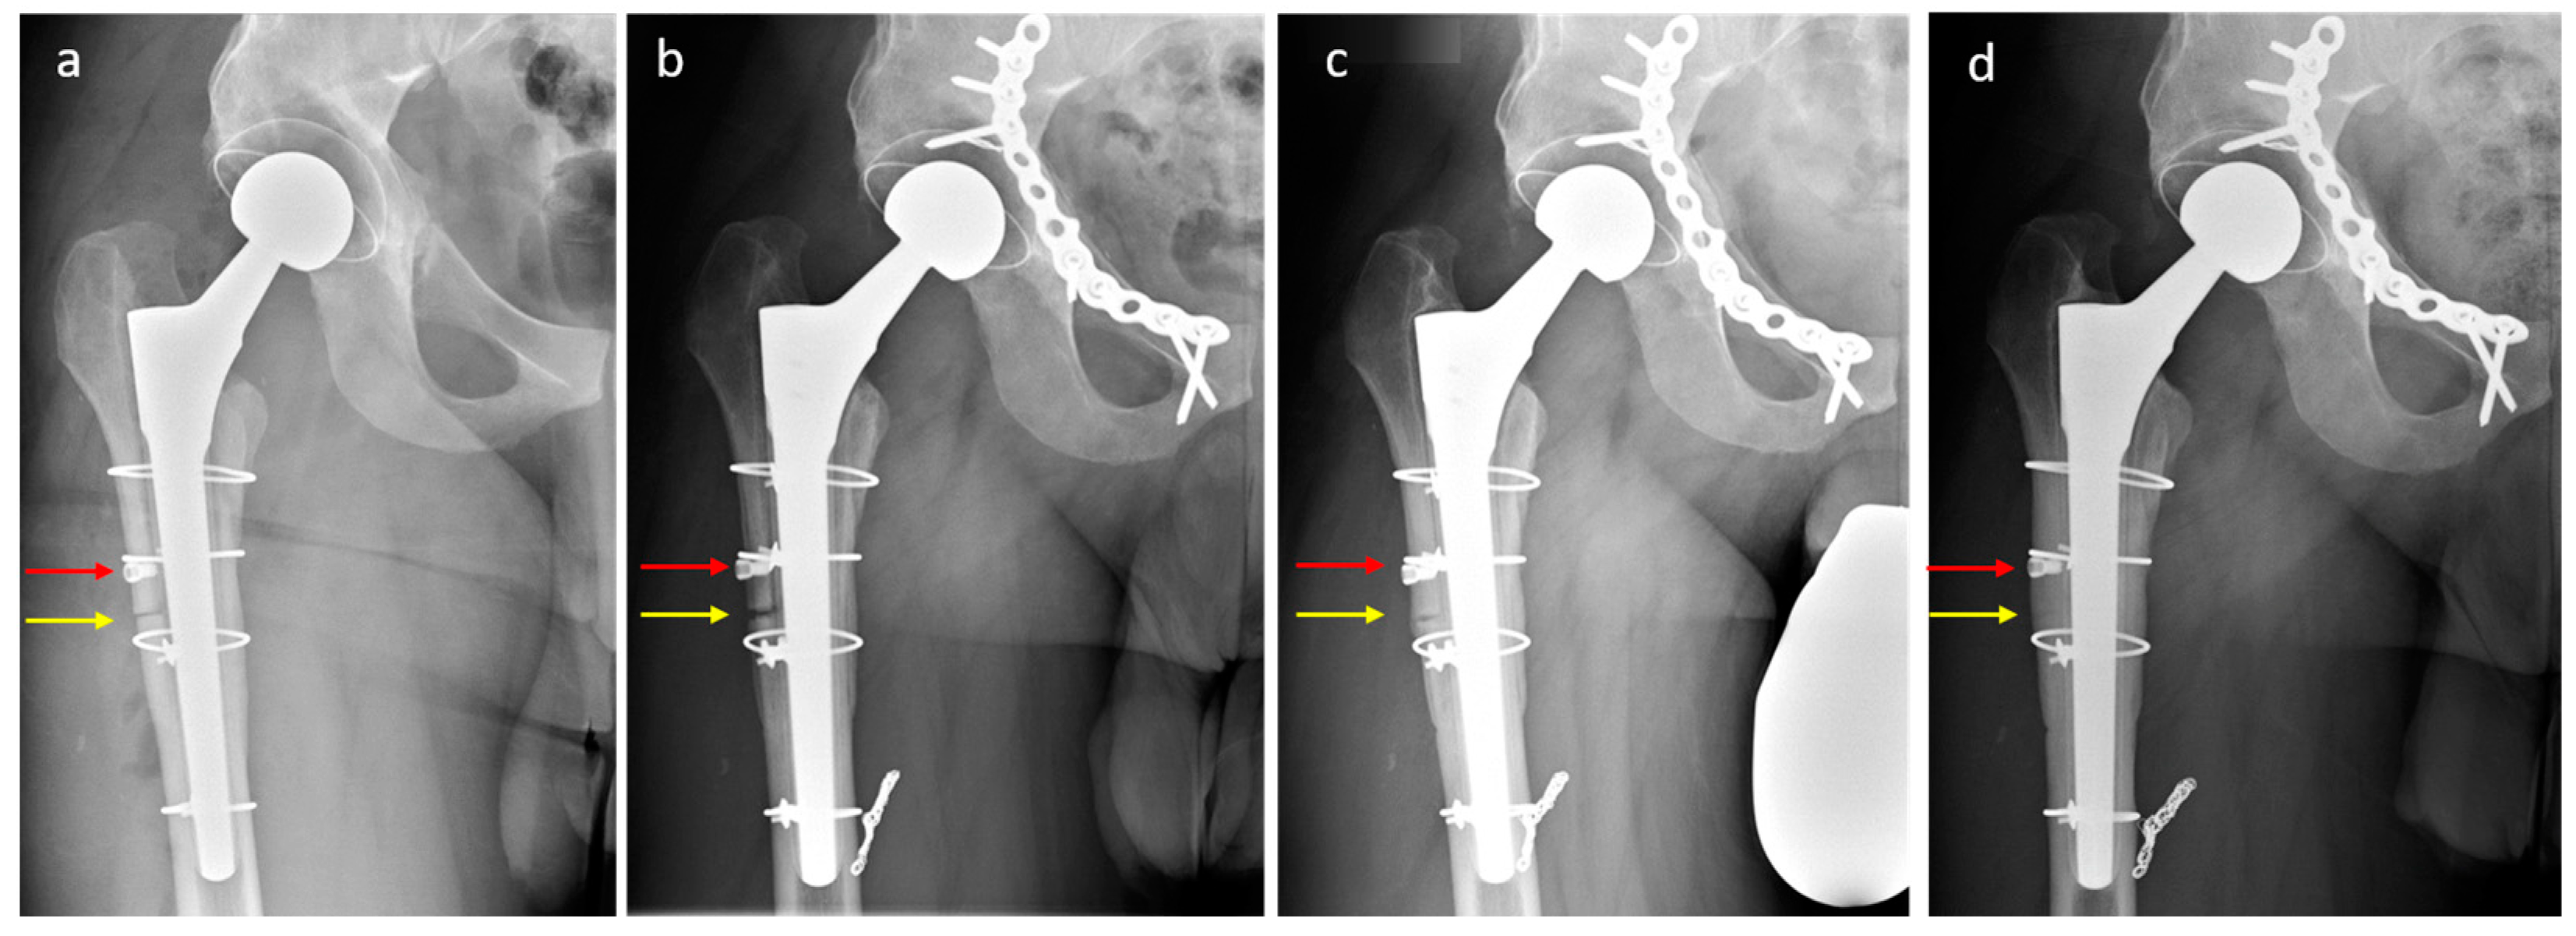

2.3.3. Clinical Case